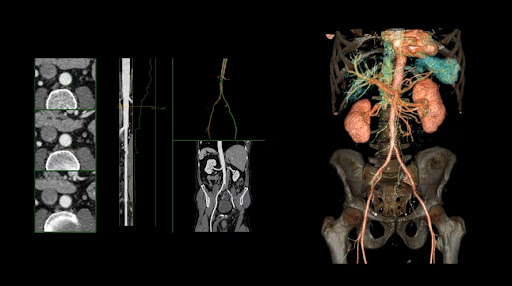

2. КТА аорты в брюшной и тазовой области, артериопортальная фаза, 6,9 мЗв**